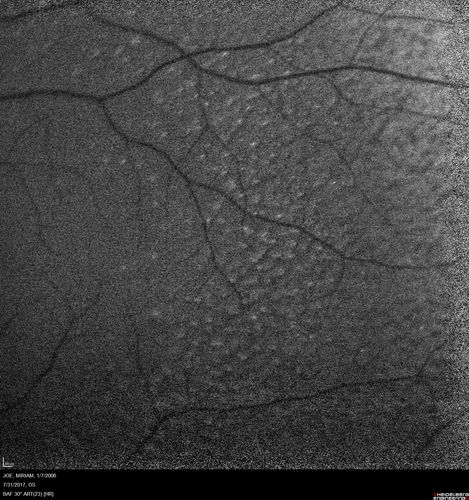

Fundus Albipunctatus

12 year old female with normal vision. She has 4 siblings all of whom have either white spots or spots on IR. Genetic testing by parents was deferred.